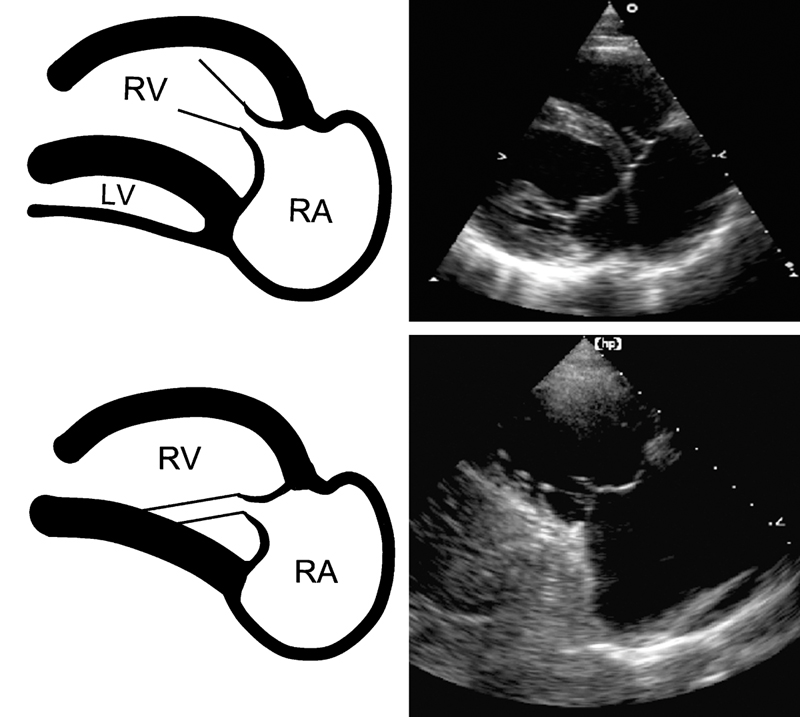

فحوصات تشخيصية لبعض امراض القلب والشرايين التاجية